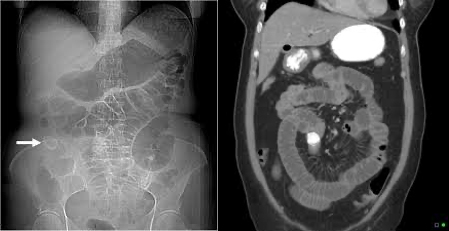

석회 담즙 및 도자기 담낭 (Limey Bile and Porcelain Gallbladder)

• 석회 담즙 (Limey Bile): 담낭 내 칼슘염 농도가 높아져 담즙이 X-ray에서 뿌옇게 보이는 상태

• 도자기 담낭 (Porcelain Gallbladder)

• 정의: 담낭 벽이 도자기(porcelain) 모양으로 석회화 되는 경우를 가리킴

• 원인: 담석에 의한 만성 염증으로 발생하는 것으로 생각됨

• 진단: 복부 X-RAY나 CT (도자기 모양의 석회화가 관찰), 초음파

• 치료: 쓸개절제술

** 담낭암 발생 위험이 높다고 알려져 예방적 절제술이 권고되어왔으나, 최근 연구에서는 그 연관성이 낮다고 보고되어 밀접한 추적 관찰도 가능